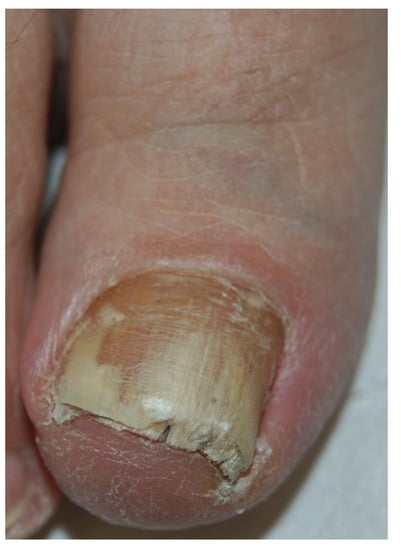

Fungi reach the nail through the hyponychium and invade the undersurface of the nail unit plate spreading proximally. Distal and lateral subungual onychomycosis (DLSO) usually affects one or both of the great toenails and is also usually associated with tinea pedis [7]. The nail plate appears yellow-white, is detached due to onycholysis, with distal subungual hyperkeratosis (Figure 1). Less frequently, a brown, black or orange discoloration of the onycholytic nail can be seen (Figure 2). A possible presentation of DLSO due to dermatophytes is dermatophytoma, a subungual accumulation of hyphae and scales, scarcely reached by antifungals, which require excision of the area and systemic treatment. DLSO may be associated with black pigmentation of the nail (“fungal melanonychia”) (Figure 3), when the pathogen is the Melanoides variant of Trichophyton rubrum or other fungi that produce melanin, like Neoscytalidium dimidiatum or Aspergillus niger [11]. Onychomycosis due to non-dermatophytes is typically associated with a marked periungual inflammation (Figure 4). Differential diagnoses of DLSO include traumatic onycholysis (usually symmetrical and subungual hyperkeratosis is absent) and nail psoriasis (diffuse hyperkeratosis, several/all toenail involved, others skin and nail signs of psoriasis).

Figure 3. Pigmented DLSO.